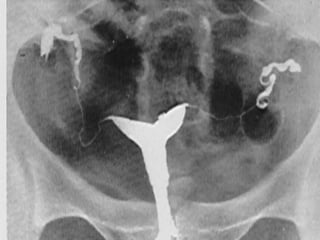

Congenital Uterine Anomaly

n  Diagnosis:

History

Pelvic exam

Hysterosalpingography

U/S

MRI

Laproscopy

Hysteroscopy

IVP or U/S (Exclude Renal anomaly )

• 12.

Congenital Uterine Anomaly n Diagnosis: History Pelvic exam Hysterosalpingography U/S MRI Laproscopy Hysteroscopy IVP or U/S (Exclude Renal anomaly )